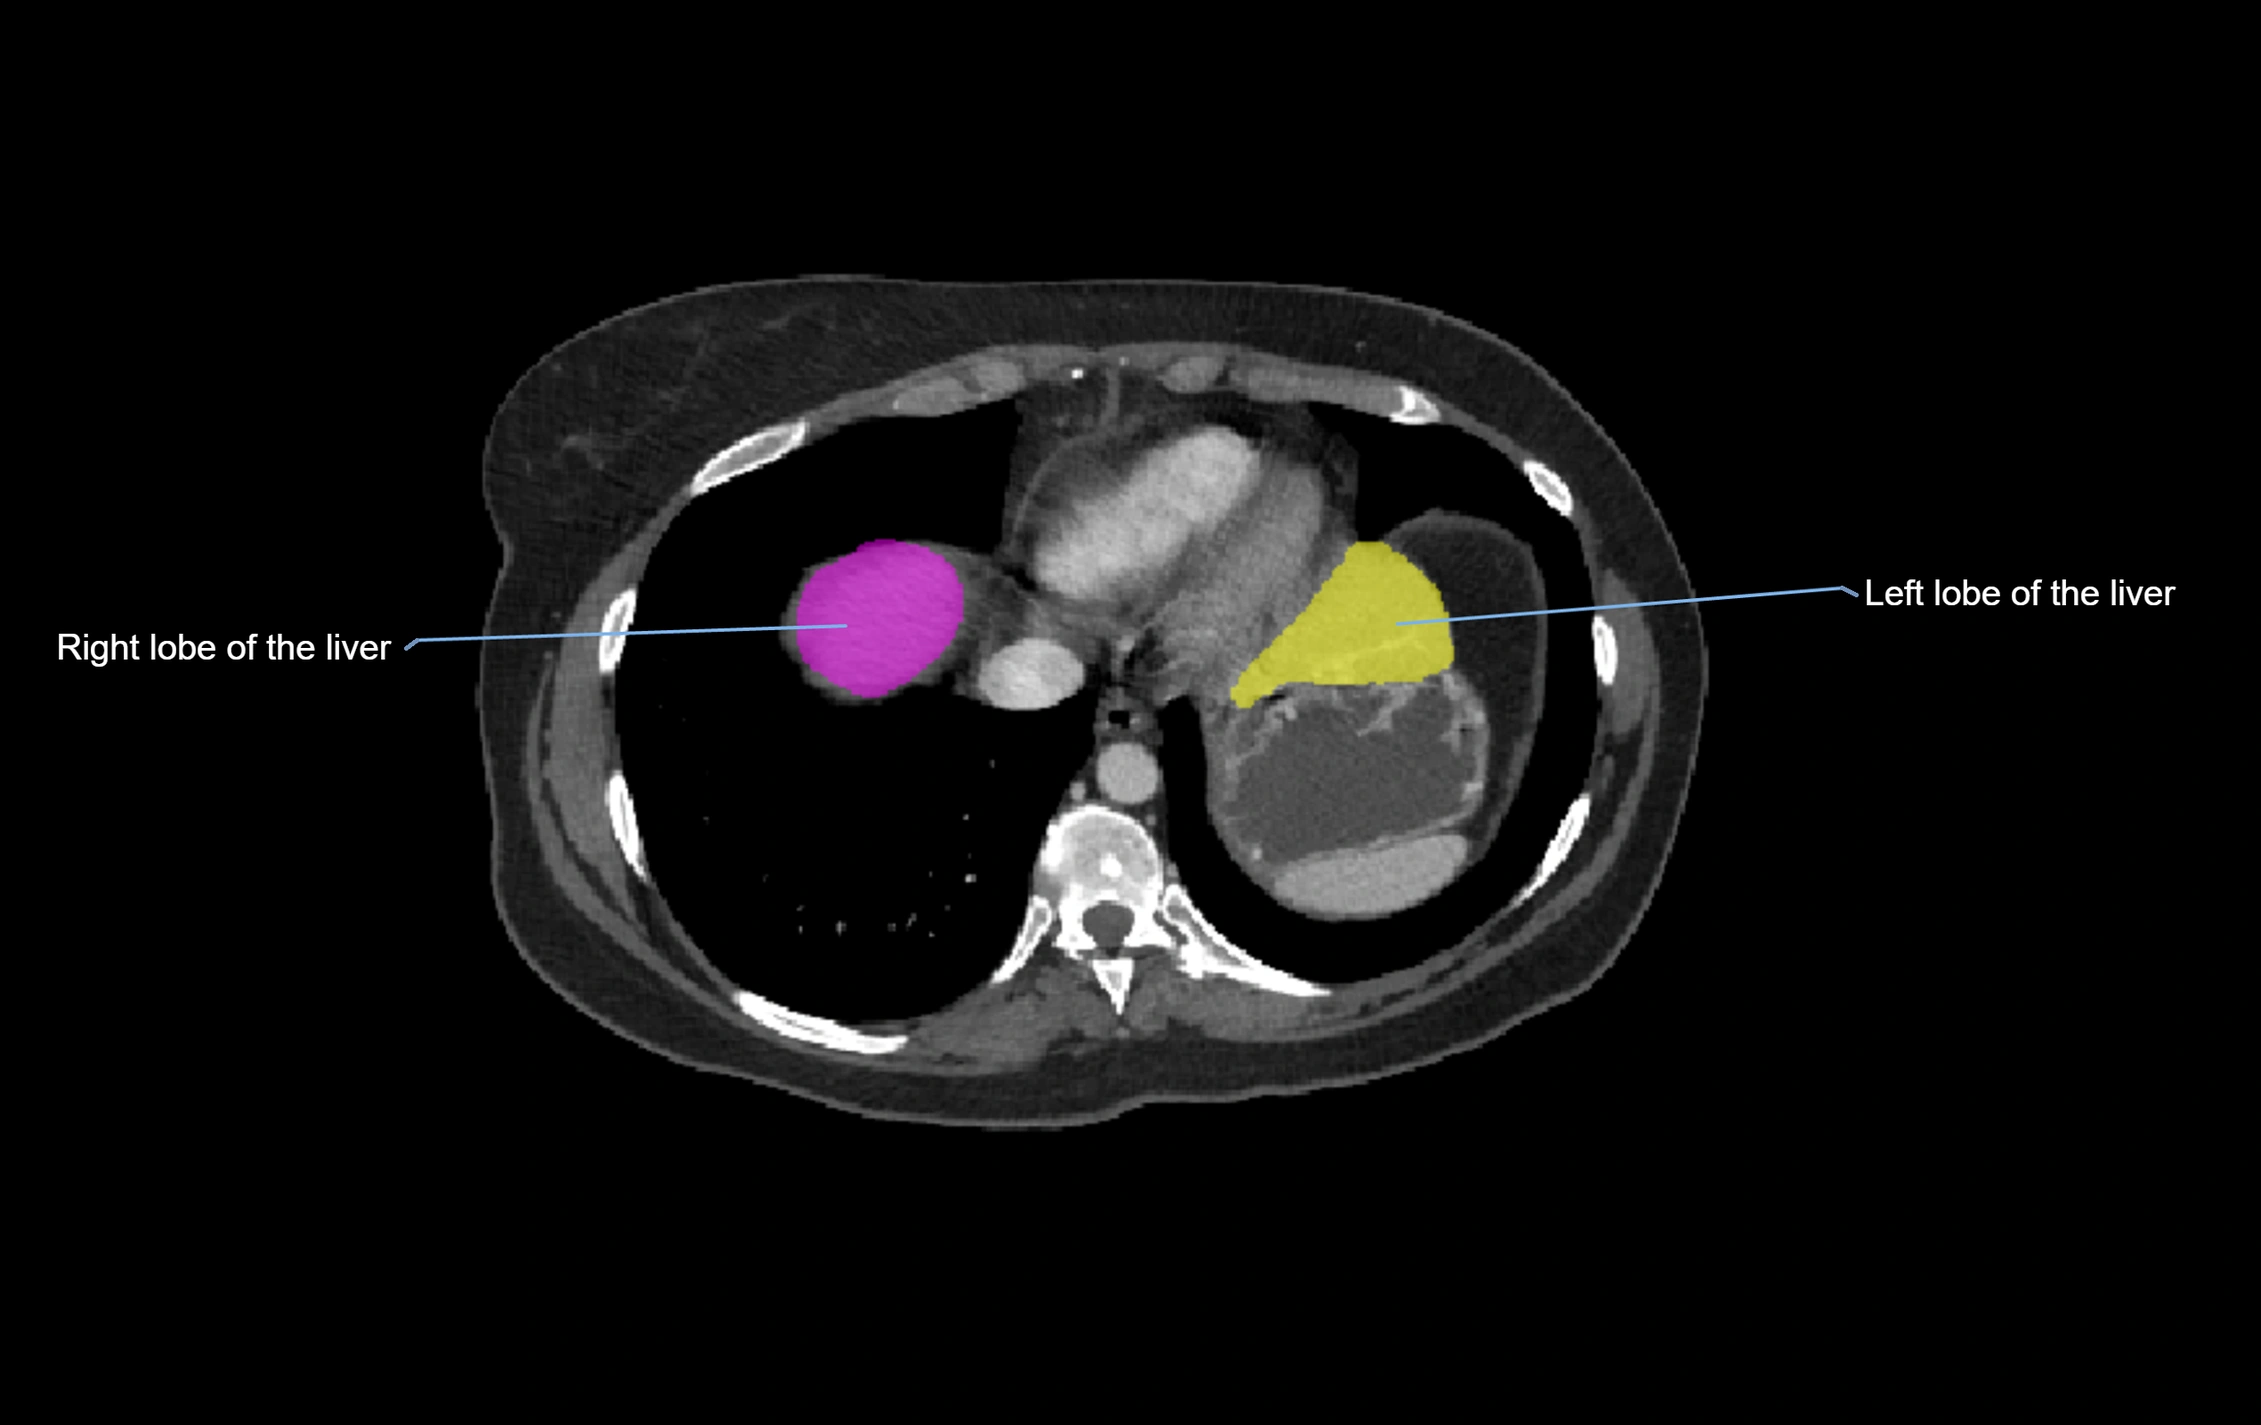

The caudate lobe of the liver is a distinct anatomical subdivision of the liver, designated as segment I in Couinaud’s classification. It lies on the posterior surface of the liver, between the fissure for the ligamentum venosum (left boundary) and the groove for the inferior vena cava (IVC) (right boundary). Superiorly, it is related to the posterior liver surface, and inferiorly it is separated from the left lobe by the porta hepatis.